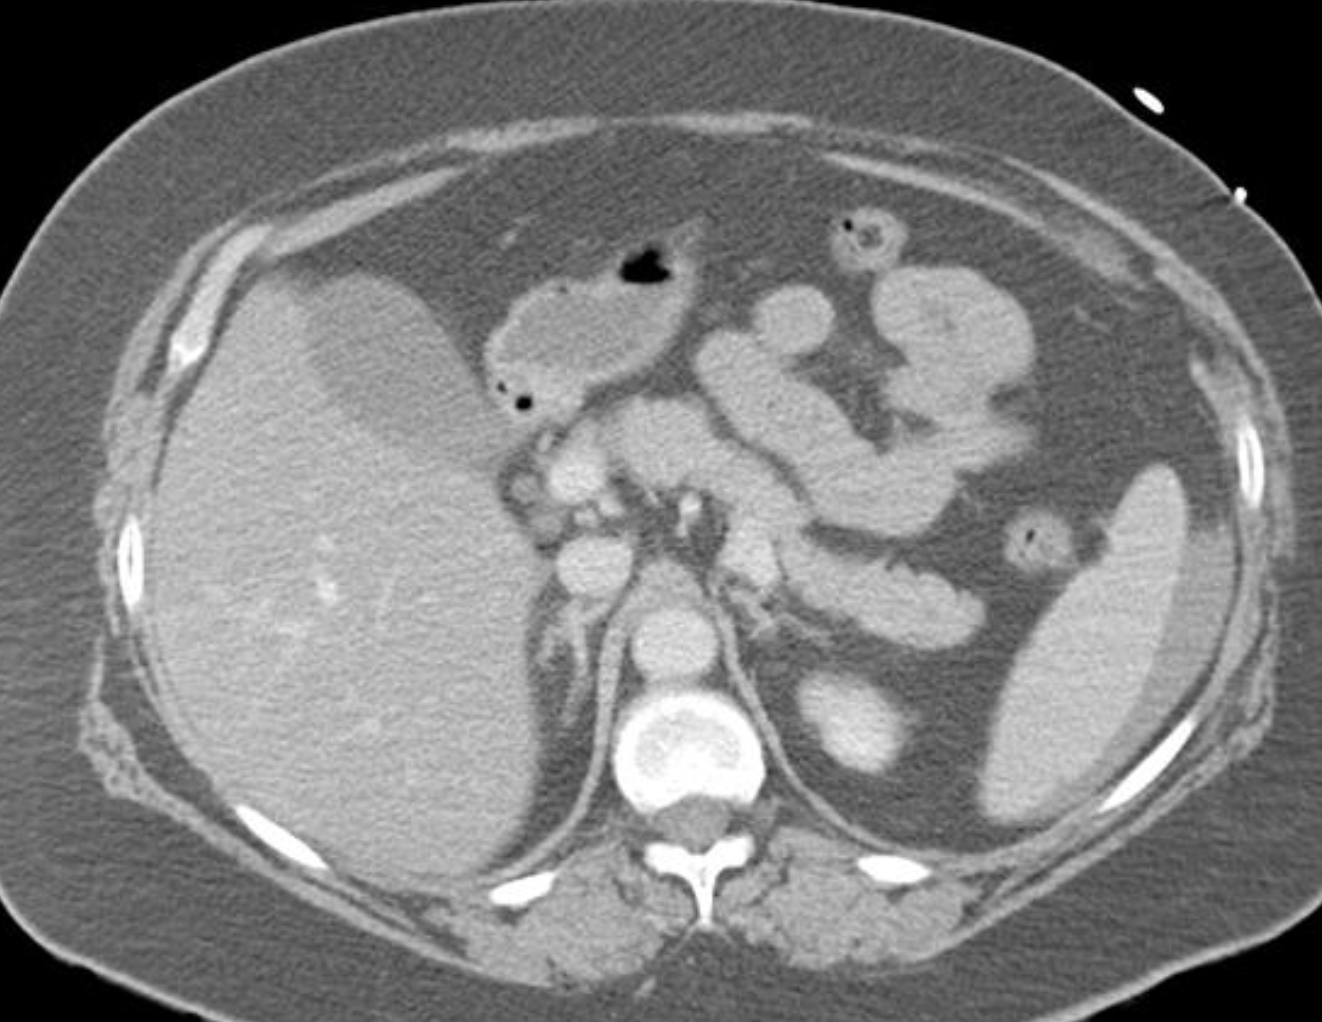

What grade Splenic injury is this?

Extensive splenic lacerations extending to the hilum with areas of devascularisation. No evidence of active bleeding or pseudo-aneurysm. There is extensive haemoperitoneum throughout the abdominopelvic cavity. Cholecystectomy clips are noted along with extrahepatic and first order intrahepatic duct dilatation. Liver is uninjured. Adrenal glands, kidneys and pancreas are uninjured. Bowel is unremarkable. Lung bases are clear. No bony injury identified.

Conclusion:

AAST grade IV splenic injury with extensive haemoperitoneum.

Case Discussion

Further history obtained (after the CT) revealed a fall from 1.5 metres. Patient proceeded to successful splenic embolisation.